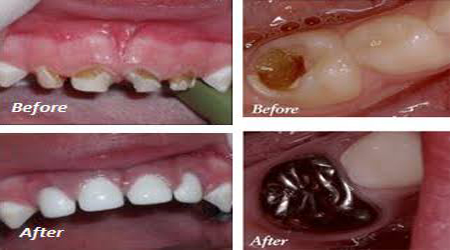

Child Dentistry

Smile For Children

Procedure INR US

Milk Teeth Filling (GIC) 800-1500 12-25

Pulpectomy (RCT) 3500-5500 50-75

Stainless Steel Crown 3500-5000 50-70

Esthetic Crown (Tooth Like) 4000-6000 55-85